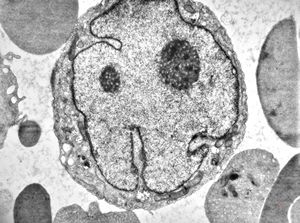

bone marrow - normoblast

F,43y. | blood - hairy cell leukemia - normoblast